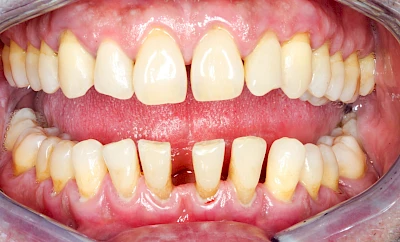

Bakterien in den Zahnbelägen greifen neben den Zähnen auch das Zahnfleisch (Gingiva) und den gesamten Zahnhalteapparat (Parodont) an. Der Körper reagiert mit einer Entzündung, sichtbar als Rötung und Schwellung. Meist blutet das Zahnfleisch z .B. beim Essen oder auch beim Putzen der Zähne.

Ist zunächst nur das Zahnfleisch von der Entzündung betroffen, spricht man von Gingivitis. Später, wenn auch der Knochen um die Zähne herum entzündet ist, spricht man von einer Parodontitis. Bei der Parodontitis wird der Knochen nach und nach abgebaut und das Zahnfleisch zieht sich zurück. Die Zahnhälse und Zahnwurzeloberflächen liegen mehr und mehr frei. Die Zähne werden zunehmend lockerer und fallen schließlich aus.